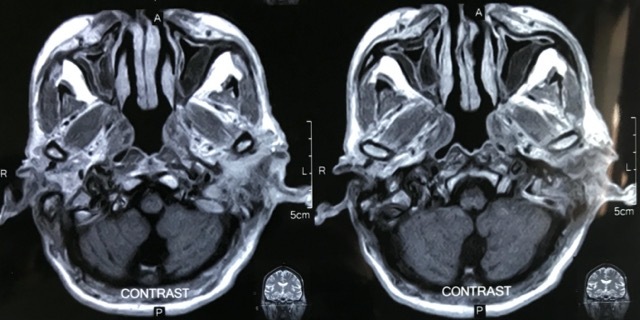

Scans

Cholesteatoma Clinical

Cholesteatoma Diagrams